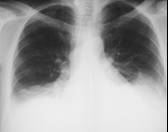

Supine

In the supine position, the fluid layers out posteriorly and produces a

haziness, especially near the bases (since the patient is actually semi-

recumbent). In the erect position, the fluid falls even more to the bases.